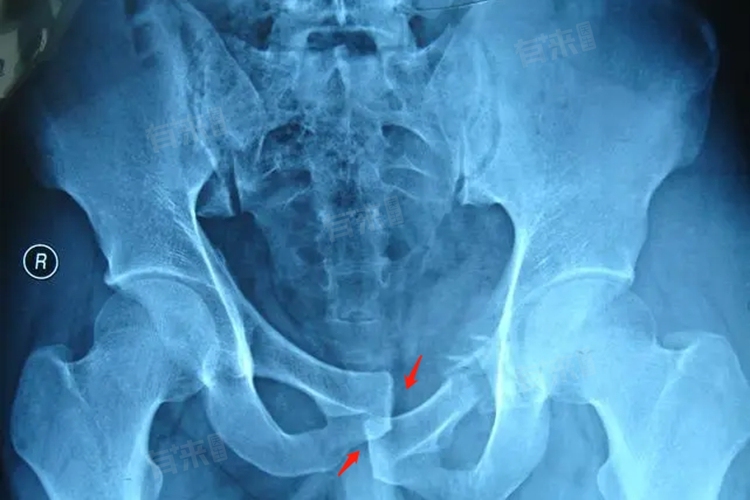

2、稳定骨盆:稳定骨盆是治疗骨盆骨折的重要环节,可以采用骨盆带、外固定支架等方法进行临时固定,以减少骨折端的移动,减轻疼痛控制出血。稳定骨盆有助于防止进一步的损伤,为骨折的愈合提供稳定的环境,在固定过程中,要注意固定的松紧度适宜,避免过紧或过松影响治疗效果。